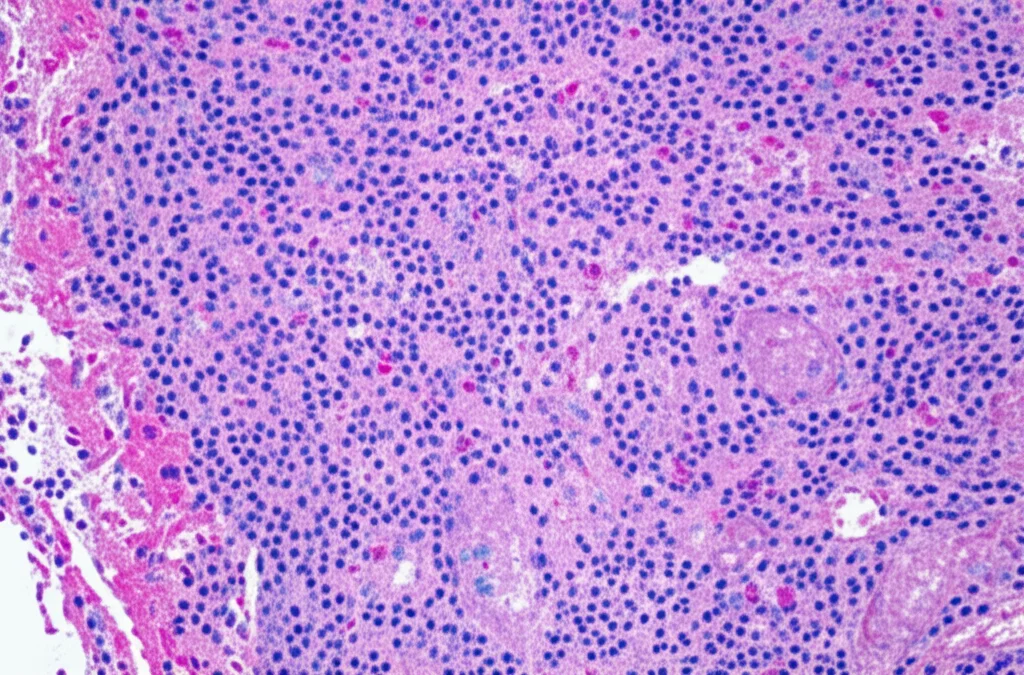

Immaginate un tipo di tumore ovarico così raro da rappresentare meno dello 0.5% di tutti i tumori dell’ovaio. Questi sono gli SLCT. Fanno parte della famiglia dei tumori dei cordoni sessuali-stromali e la loro particolarità sta nella grande varietà con cui si presentano, sia dal punto di vista clinico che istologico (cioè, come appaiono al microscopio). A volte causano sintomi legati agli ormoni maschili (virilizzazione), altre volte sintomi più generici come masse addominali. Questa variabilità li rende spesso una sfida diagnostica. Tradizionalmente, li classifichiamo in base al grado di differenziazione delle cellule tumorali e alla presenza di certi pattern specifici.

Per capirci di più, abbiamo condotto uno studio retrospettivo, andando a “rivedere” i casi di 50 pazienti con diagnosi di SLCT seguiti presso il Peking Union Medical College Hospital tra il 1994 e il 2022. Abbiamo analizzato il DNA estratto dai tessuti tumorali (conservati in paraffina) per cercare specificamente le mutazioni hotspot nel gene DICER1, usando la tecnica del sequenziamento Sanger. Parallelamente, abbiamo raccolto tutte le informazioni cliniche disponibili: età delle pazienti alla diagnosi, sintomi, stadio del tumore secondo la classificazione FIGO, decorso della malattia (follow-up), eventuali recidive. Ovviamente, abbiamo riesaminato attentamente anche le caratteristiche patologiche dei tumori al microscopio: grado di differenziazione (ben differenziato, intermedio, scarsamente differenziato), pattern di crescita, presenza di particolari strutture come quelle retiformi, aspetto dello stroma (il tessuto di supporto), presenza di emorragie, numero di mitosi (indice di proliferazione cellulare) e l’indice Ki-67 (un altro marcatore di proliferazione). Abbiamo anche guardato l’infiltrato infiammatorio, in particolare le cellule T (CD3+) e B (CD20+), e l’espressione di PD-L1, un marcatore legato alla risposta immunitaria.

E qui arrivano i risultati più succosi! Su 50 casi analizzati con successo, 15 (il 30%) presentavano mutazioni hotspot di DICER1. La prima scoperta fondamentale è stata questa: le mutazioni di DICER1 si trovano esclusivamente nei tumori a differenziazione intermedia o scarsa (ne abbiamo trovate nel 35.7% di questi), mentre nessuno dei tumori ben differenziati le presentava. Questo rafforza l’idea, già proposta da altri ricercatori, che gli SLCT ben differenziati e quelli meno differenziati potrebbero essere due entità biologicamente distinte, con origini diverse.

- Morfologia al microscopio: I tumori mutanti mostravano più frequentemente caratteristiche specifiche:

- Componenti retiformi (un pattern che ricorda una rete): presenti nel 40% dei casi mutanti, 0% nei wild-type.

- Disposizione a cordoni o nastri: 33.3% nei mutanti vs 7.4% nei wild-type.

- Stroma mucinoso edematoso (un aspetto “gelatinoso” del tessuto di supporto): 80% nei mutanti.

- Emorragie diffuse: 80% nei mutanti.